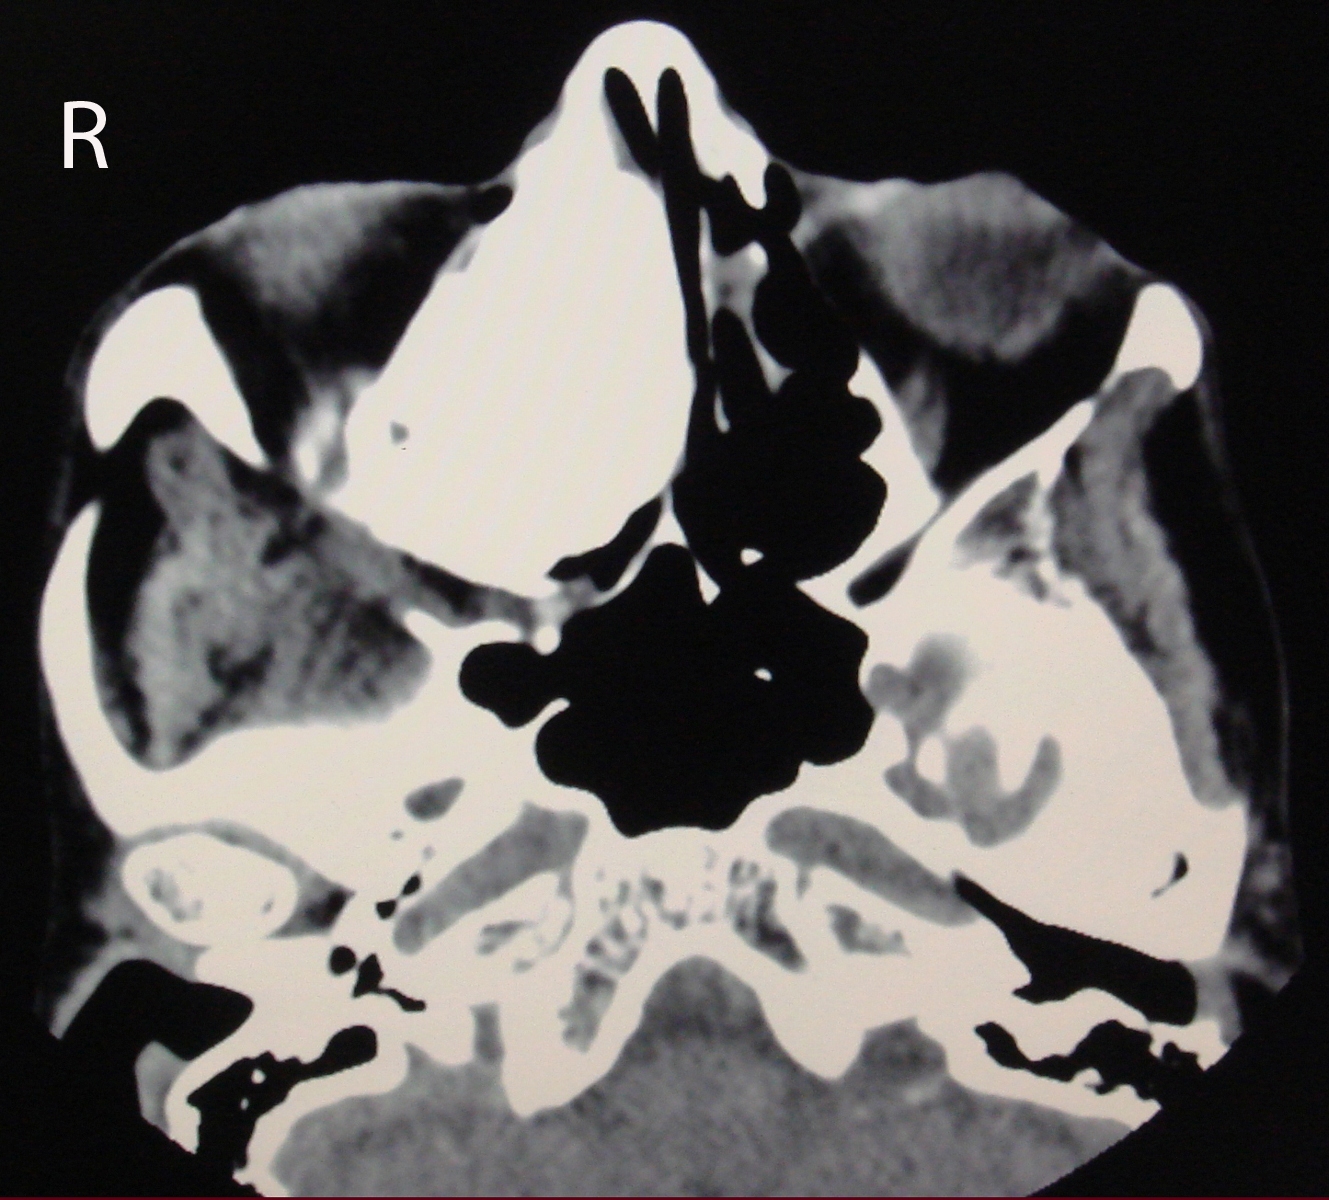

Osteoma is the most frequent benign tumor of paranasal sinuses. Usually osteomas are asymptomatic and discovered incidentally during radiological imaging for other reasons. A giant osteoma with intraorbital extension is rare. Plain radiograph may be useful; however CT scan is the best modality of investigation for diagnosing and treatment planning. In asymptomatic osteomas, serial follow-up can be done. Surgery is performed in the presence of symptoms and signs. We report a case of 60 years old woman with a large osteoma of right ethmoid sinus extending into the ipsilateral orbital cavity.